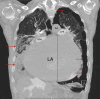

An Audaciously Aneurysmal Atrium

Keywords: Echocardiography; Imaging; Mitral stenosis; Rheumatic heart disease.